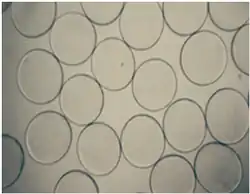

The diameter of the microcapsules is an important factor that influences both the immune response towards the cell microcapsules as well as the mass transport across the capsule membrane. Studies show that the cellular response to smaller capsules is much lesser as compared to larger capsules[64] and in general the diameter of the cell loaded microcapsules should be between 350-450 μm so as to enable effective diffusion across the semi-permeable membrane.[65][66]